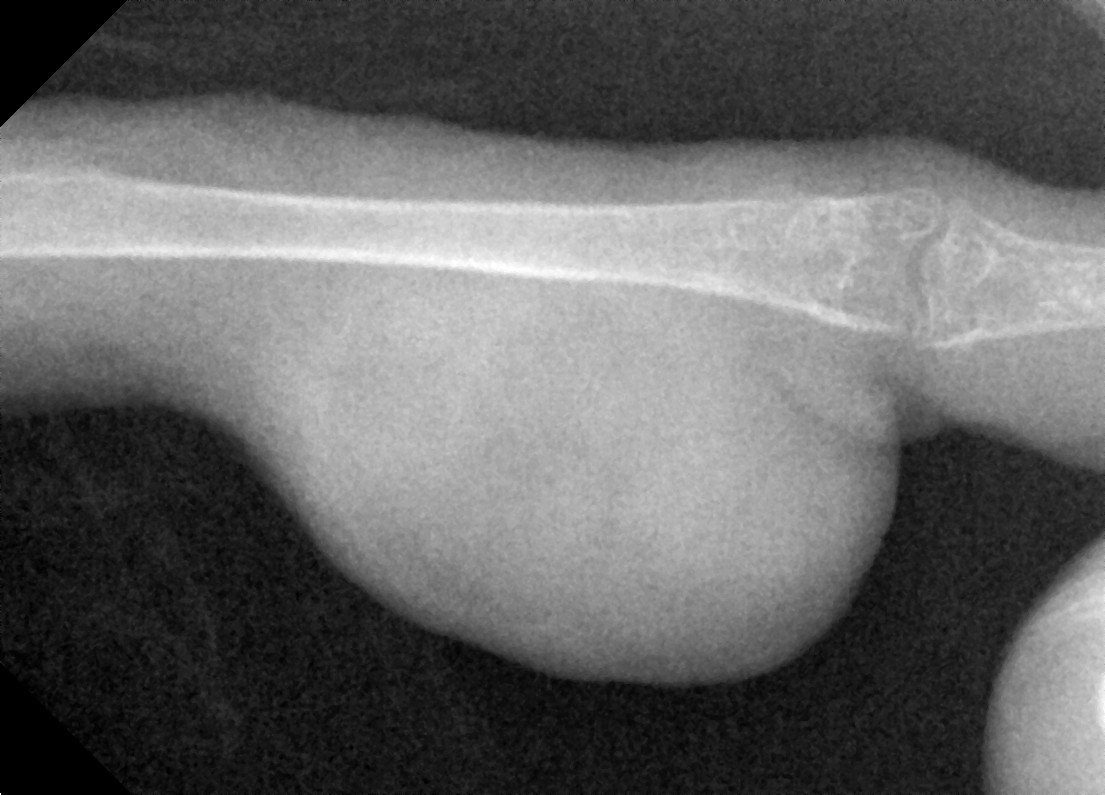

Dukemc Опубликовано 11 января, 2020 #1 Опубликовано 11 января, 2020 (изменено) 2. Корелла 3. Самец, 4-5лет 4. Престиж бельгия, сепия, мин камень, фрукты почти не ест, при линьке давали витамины "витакрафт линька", вода - осмос 5. 20-22град. Клетка на окне без сквозняков 6. После появления ребенка стал менее подвижен, очень мало летает уже больше как полутора лет, аппетит хороший, но 4мес назат появилась опухоль лапки, мазали траумелем но опухоль увеличилась, раньше вроде неудобств у попугая небыло, на лапе спал. Опухоль твердая, на вид круглая но как будто набита бугорками фото с сентября Изменено 11 января, 2020 пользователем Dukemc

Dukemc Опубликовано 11 января, 2020 Автор #2 Опубликовано 11 января, 2020 фото сейчас, лапа в щиколотке стала толще, на подушке появилися натоптыш

Zosia Опубликовано 30 января, 2020 #16 Опубликовано 30 января, 2020 Кость целая,без патологических изменений, без зон распада или абсцессов Броди. Возможно есть какие-то проблемы в суставе (кажется низковатой плотность, возможно след старой травмы СУСТАВА). Я сделала инверсию снимка, видится некое образование,кистоподобное, на латеральной проекции. Возможно исходит из суставной сумки (цифра 1). Это м.б. абсцессом, гигромой- но связано скорее всего с соедигнительной тканью. На склеродермию или подагрическое образование непохоже. На ВД проекции в нижней четверти кости есть (возможно это артефакт) некое нарушение четкой границы кости (цифра 2)... но параметры снимка не позволяют с уверенностью эту неровность оценить. Вопросы: Есть ли проблемы с дыханием Есть ли проблемы с пищеварением (рвота напрмиер) И нужен рентген "всей птицы", хотя бы один...

Zosia Опубликовано 1 февраля, 2020 #27 Опубликовано 1 февраля, 2020 На второй лапе- зона артроза или подагрических отложений (четкости никакой).